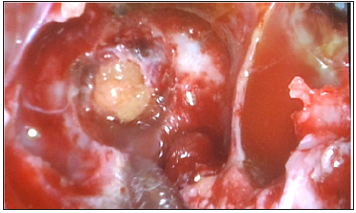

A 36 -year-old female was admitted for three weeks of clear watery discharge from the right nostril, which was aggravated in prone position. The patient denied any recent trauma. A review of systems was negative except for headaches and nasal discharge. The nasal fluid tested positive for beta-2 transferrin, indicating that the fluid was CSF. Brain MRI revealed that the sphenoid sinus was filled with Cerebrospinal Fluid (CSF) and sagittal T2 weighted MRI revealed a fistula tract from prepontine cistern to sphenoid sinus (Figure 1). There was no evidence of benign intracranial hypertension. Computed tomography cisternography revealed that the contrast material passed from the prepontine cistern into the sphenoid sinus through this bone defect in the clivus (Figure 1). Before surgery, a lumbar puncture was performed to administer 0.25mL of 10% fluorescein with 10mL of Cerebrospinal Fluid (CSF) to help visualize CSF leaks during surgery and to ensure there was no leak after reconstruction of the defect. The patient underwent endoscopic trans nasal transsphenoidal surgery. The anterior and middle portions of the clivus were exposed between both carotid arteries. During surgery, the defect was defined to the left of the midline in the clivus. The basilar artery was seen through the defect in prepontine cistern (Figure 2). The defect was closed with a multilayer reconstruction consisting of fat, fascia lata, and naso septal flap (Figure 3). There was no recurrence of CSF leak at 2 years follow-up.

Figure 2:(a) Intraoperative endoscopic view show CSF leakage from clivus defect just inferior to sella .(b) basilar artery in prepontine cistern behind the defect.

Figure 3: Endoscopic view pos repair with abdominal fat.